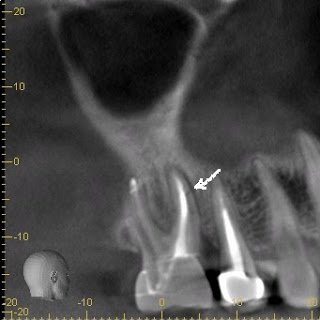

Rotation of the image, giving a palatal view of #14, shows a horizontal fracture in the MB root.

With these radiographic findings as well as the clinical findings, a confident diagnosis of vertical root fracture can be made. Extraction was recommended in